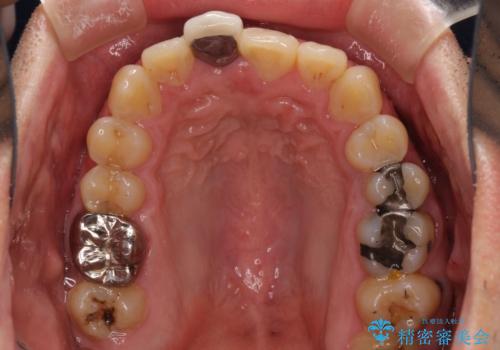

- 前歯のデコボコと上下のクロスバイトを気にして来院された患者様です。

インビザラインを用い、IPR(歯と歯の間を削る)と歯列全体を拡大させることで、歯並びを整えていくこととしました。

上の前歯が下の前歯を乗り越える際、奥歯がほとんど咬めない時期があり、乗り越えた後も、インビザライン特有の奥歯の咬みにくさが続きました。

咬み合わせ改善のために治療期間を要しましたが、最終的に奥歯はしっかりと咬めるようになりました